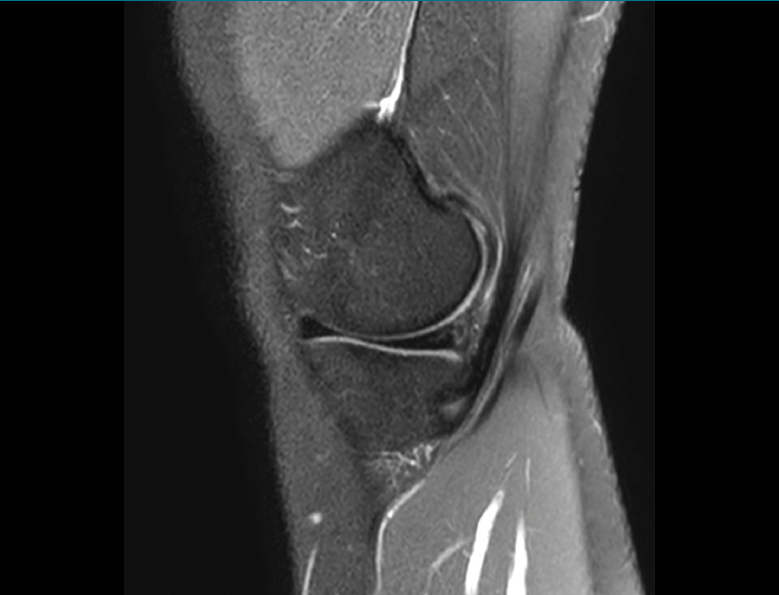

1.2. Ligamentos

Se visualizan como estructuras lineales hipointensas en todas las secuencias.

1.2.1. Ligamentos laterales

Figura 36. Corte de secuencia coronal T2 Fat-Sat: ligamentos colaterales normales.

Ligamento lateral interno (LLI) y ligamento lateral externo (LLE) (Figuras 36, 37, 38 y 39).